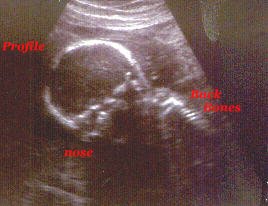

I got a good profile.